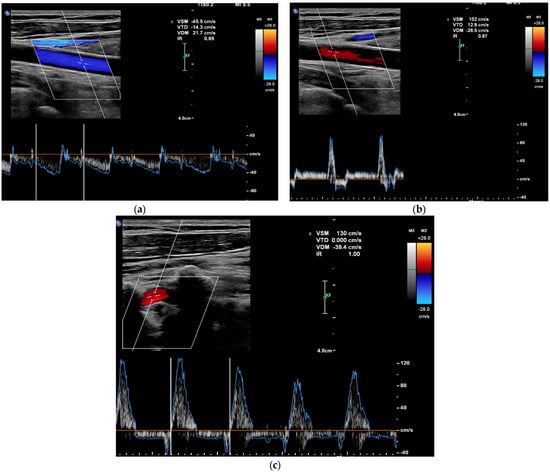

In addition, multiple vascular Doppler ultrasound (DUS) studies were performed. The first vascular Doppler study found no anatomical explanation for the anisotension. The second vascular Doppler ultrasound was performed during the critical phase of a lipothymic episode and showed a complete steal syndrome of the left carotid and vertebral arteries defined by a reversal of blood flow direction, with a contralateral hyperflow of the right carotid artery, which stopped after syncope (Figure 3). On colour and pulsed Doppler, there was a reversal in the direction of flow (antidromic) of the left internal carotid and vertebral arteries during the symptoms. At the end of the episode, the pulsed and colour Doppler analysis showed an intermittent flight of the left internal carotid artery and of the vertebral arteries defined by a reversal of the direction of blood flow in diastole.

Figure 3.

Colour and pulsed Doppler ultrasound on vascular Doppler ultrasound images. (a) Pre-critical left internal carotid artery with complete carotid flight. (b) Post-critical left internal carotid artery with intermittent carotid flight. (c) Post-critical left vertebral artery with intermittent carotid flight.